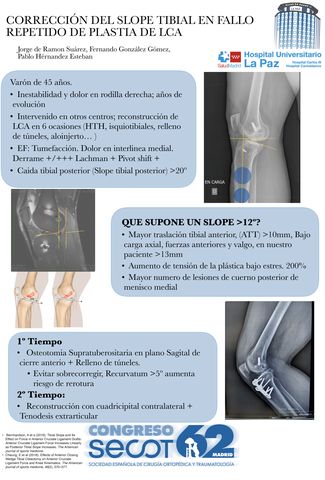

En el quirófano como el mar quiero ser único al navegar. Doble osteotomía navegada con placas personalizadas.

ANTONIO JAVIER SUÁREZ MILLÁN, ABEL PÉREZ SÁNCHEZ, JOAQUIN MOYA-ANGELER PEREZ-MATEOS, EVA FERNÁNDEZ DÍAZ, FRANCISCO LAJARA MARCO